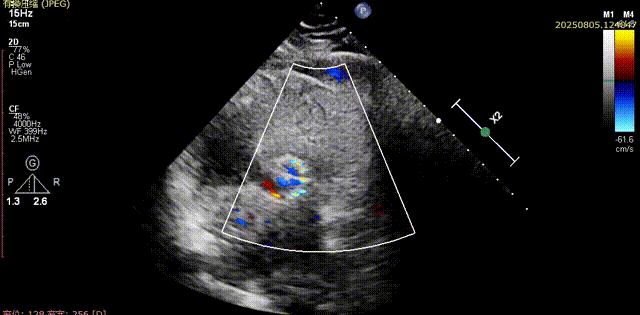

术前胸骨旁长轴切面可见流出道结构良好,五腔心切面可见主动脉瓣少中量反流

流出道结构观察

五腔心切面观察